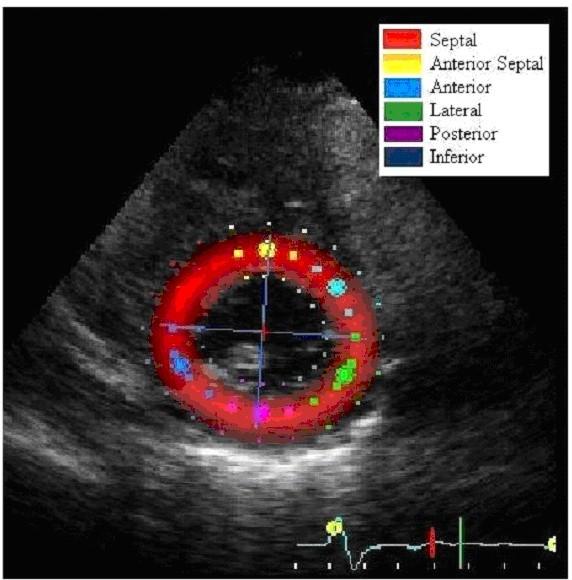

We evaluated 30 patients with CTEPH before and after PTE using 2D speckle tracking measurements of LV radial and circumferential strain and SR in the short axis, and correlated the data with right heart catheterization (RHC).

PTE resulted in a decrease in mean PA pressure (44 ± 15 to 29 ± 9 mmHg), decrease in PVR (950 ± 550 to 31 ± 160 [dyne-sec]/cm⁵), and an increase in cardiac output (3.9 ± 1.0 to 5.0 ± 1.0 L/min, p < 0.001 for all). Circumferential and posterior wall radial strain changed by -11% and +15% respectively (p < 0.001 for both). Circumferential SR and posterior wall radial SR changed by -7% and 6% after PTE. While the increase in posterior wall SR with PTE reached statistical significance (p = 0.04) circumferential SR did not (p = 0.07). In addition, septal radial strain and SR did not change significantly after PTE (p = 0.1 and 0.8 respectively). Linear regression analyses of circumferential and posterior wall radial strain and SR revealed little correlation between strain/SR measurements and PVR, mean PA pressure, or cardiac output. However, change in circumferential strain and change in posterior wall radial strain correlated moderately well with changes in PVR, mean PA pressure and cardiac output (r = 0.69, 0.76, and 0.51 for circumferential strain [p < 0.001 for all] and r = 0.7, 0.7, 0.45 for posterior wall radial strain [p = 0.001, 0.001, and 0.02, respectively]).

LV circumferential and posterior wall radial strain change after relief of pulmonary arterial obstruction in patients with CTEPH, and these improvements occur rapidly. These changes in LV strain may reflect effects from improved LV diastolic filling, and may be useful non-invasive markers of successful PTE.